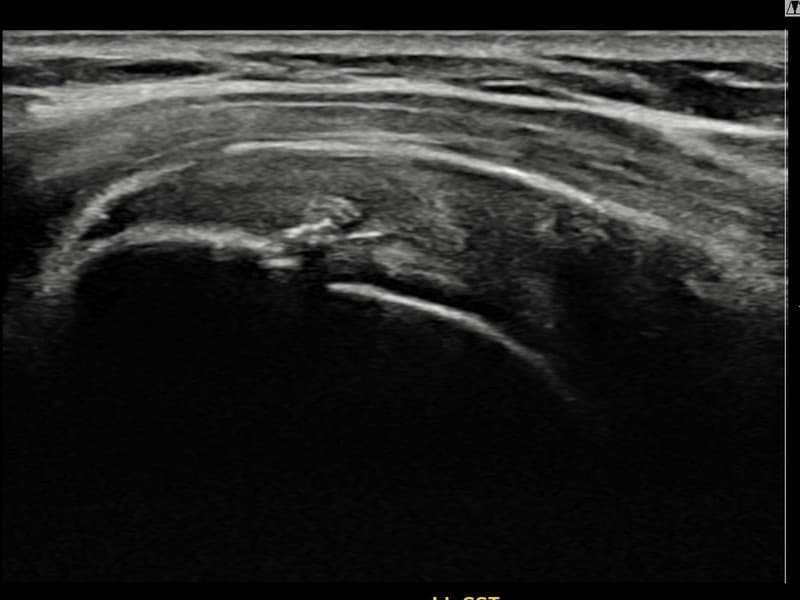

After

시술 전 초음파 측정 결과 파열 크기는 8mm × 3mm (힘줄 두께의 약 30% 결손)로 확인되었습니다. 시술 전 초음파에서 좌측 극상근건 관절면측의 에코 소실과 힘줄 경계 불명확화가 확인되었습니다. 시술 후 초음파에서 관절면측 힘줄 경계가 선명해지고 에코 패턴이 정상으로 회복된 것이 관찰되었습니다.

40대 후반 여성 환자분으로, 테니스를 즐겨 하시다 왼쪽 어깨에 통증이 생겨 운동을 중단하셨습니다. 이후 일상적인 동작에서도 통증이 지속되어 내원하셨으며, 초음파 검사에서 좌측 극상근건 관절면측 부분파열이 확인되었습니다. 파열 범위가 비교적 초기 단계이나 방치 시 진행될 수 있어 조기에 초음파 유도 하 축소봉합술을 시행하였습니다. 시술은 20분 이내에 완료되었고 당일 귀가하셨으며, 보조기 착용 4주 후 단계적 운동 복귀 프로그램을 진행하였습니다. 시술 13주 후 추적 초음파에서 극상근건 관절면측 연속성이 완전히 회복된 것이 확인되어 테니스 복귀에 성공하셨습니다.